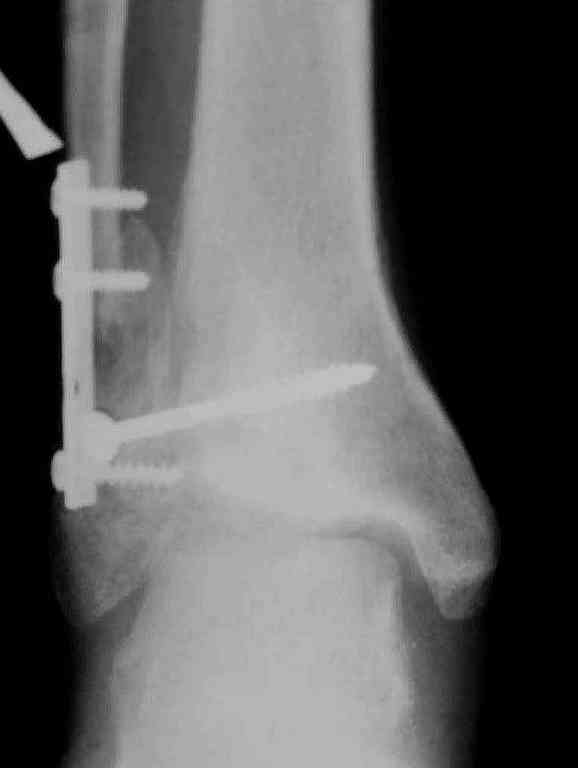

Вторая пациентка 34 лет, перелом получала в Испании, где от операции отказалась, дома по приезду сняла скотчкаст и лечилась у костоправов, нагрузка с 3 недели. Операция через 3 мес после травмы. Остеотомия м-б кости, фиксация пластиной, восстановление МБС. Так как медиальная лодыжка подтянулась, суставная щель на ЭОП контроле нормализовалась ограничились латеральным доступом. Реконструкцию заднего края не пытались сделать тк там уже прослеживалась консолидация, а сминать эпиметафиз не хотелось. В настоящее время ходит с тростью \три месяца после операции\, сустав нестабилен-слабость дельтовидной связки. Супинатор и плотные кроссовки дают возможность длительно ходить. Первый снимок сделан в Испании после репозиции, второй через 2 месяца после травмы перед операцией, третий-через 3 мес после операции.

Спасибо за вложенную схему , ранее она нам не попадалась.Согласен с Алексеем, что в обоих случаях не удалось восстановить длину фибулы.По вопросу о МБС, в первом случае после 8 месяцев синдесмоз был выполнен плотной рубцовой тканью, которую необходимо было убрать для репозиции фибулы в вырезку и винт действительно был введен с компрессией, во втором случае МБС не открывался и компресии не задавлось.Может дистрофия эпифиза все же следствие 5 месячной нагрузки с нестабильным суставом и компрессии тараном, тк вес пациента достаточно высок. По второму наблюдению необходимо определиться с тактикой, при пронации стопы отчетливо определяется слабость дельтовидной связки-перерастянута ходьбой в нестабильном суставе? Показана ли надлодыжечная варизующая остеотомия?

По снимкам в первом случае, укорочение малоберцовой приблизительно около 8-10 мм. Удовлетворительным восстановлением длины малоберцовой считается, когда на снимке суставная щель равны со всех сторон.

Несмотря на прошедшее время с момента травмы и попытки восстановления, мы бы рекомендовали повторить процедуру по сохранению сустава. Для этого очищается синдесмоз от фиброза, удлиняется малоберцовая на мортизной ренгенограмме засчет проксимальной поперечной остеотомии вставлением расширящего инструмента (lamina spreader).